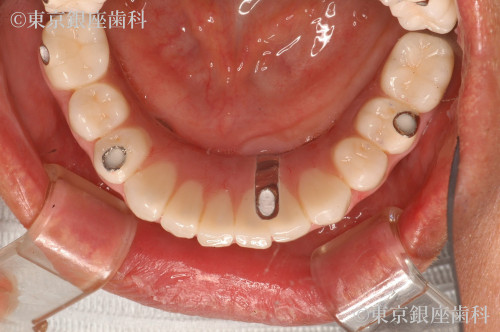

After

50代 女性

疾患 歯周病

施術内容 ワンデイインプラント

治療期間 11か月 費用 670万円(税込)

ワンデイインプラントで審美を回復

上下のワンデイインプラントを実施

鳥貌を改善